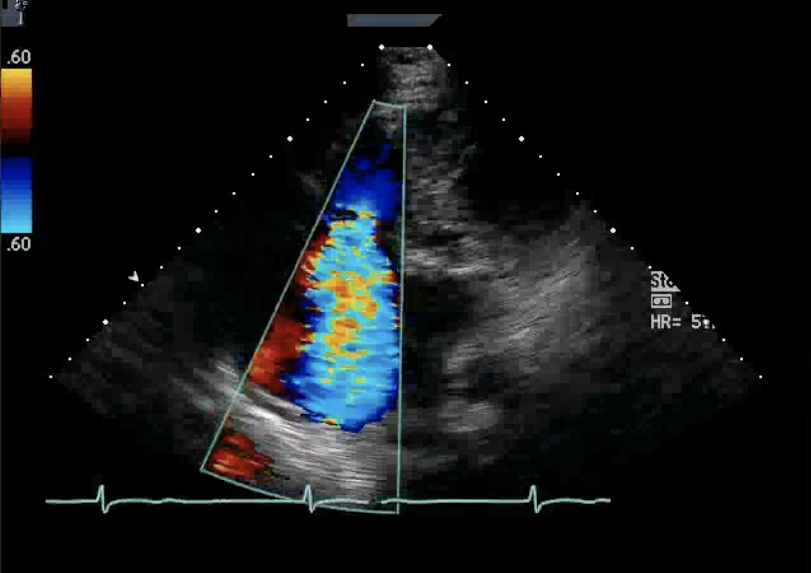

Doppler evaluation of mild TR demonstrates?

Parabolic waveform

Doppler evaluation of severe TR demonstrates?

Triangular waveform